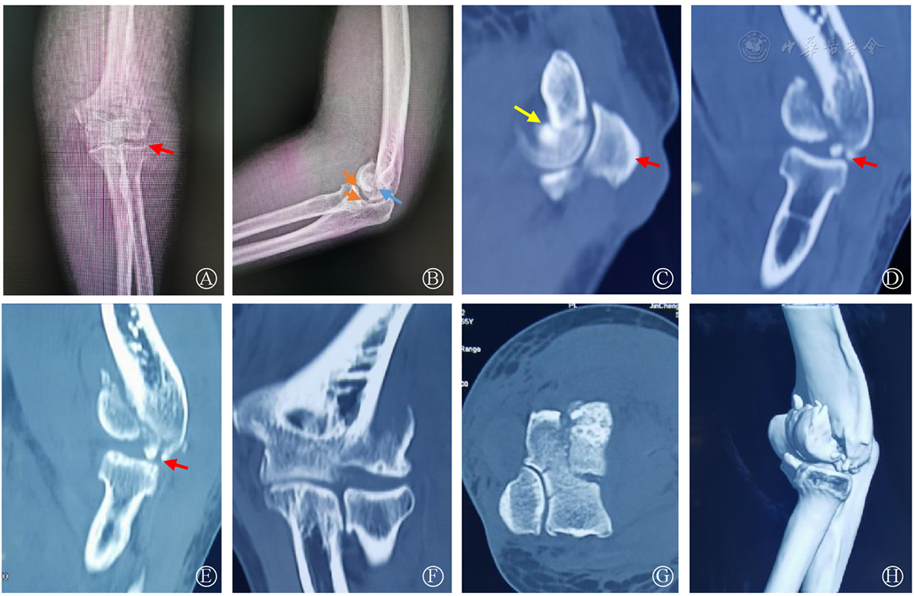

图1 术前X线及三维CT 图A:肘关节正位片可见碎骨块(红色箭头),肱桡关节关系基本正常;图B:肘关节侧位片可见"双弧征"(橙色箭头),骨折线(蓝色);图C:CT重建片可见尺骨鹰嘴(红色箭头)平面骨折提示滑车部受累(黄色箭头);图D-E:CT重建片可见肱骨小头后侧皮质粉碎(红色箭头);图F-H:术前CT重建的其他位置像